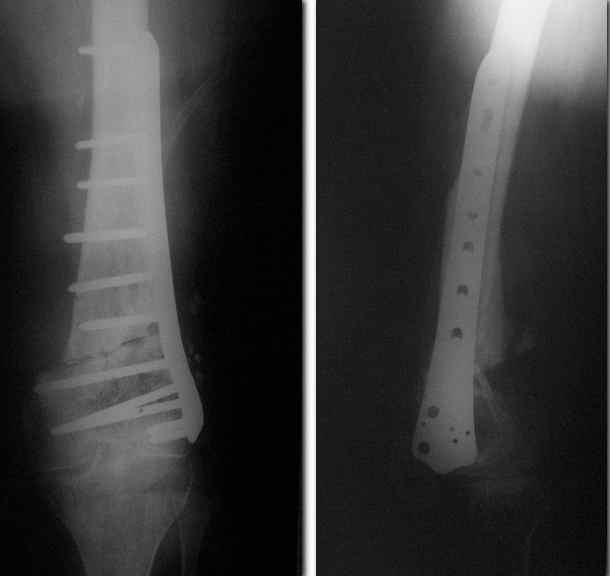

Спасибо. Прооперировали во вторник.

Выглядит красиво. А движения в колене какие были на столе?

Была контрактура и спаянный с суставной поверхностью надколенник. Сделали до синтеза редрессацию. Достигли почти полного объема движений.